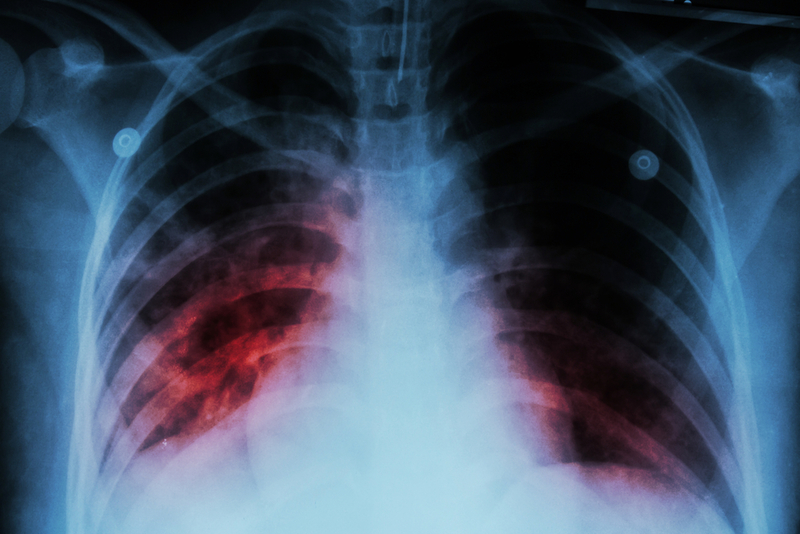

Experiments showed that within five days after infection, ILC3 cells show up in the lungs, where they release chemical compounds that activate and attract other immune cells. The arriving cells include other innate immune cells - which come loaded with bacteria-killing weapons - as well as adaptive immune cells that direct and enhance the innate immune cells' killing potential. Together, the immune cells surround the bacteria and destroy them. "These innate lymphoid cells seem to orchestrate all the early downstream immune responses, both innate and adaptive, that you need to control infection," noted Khader.